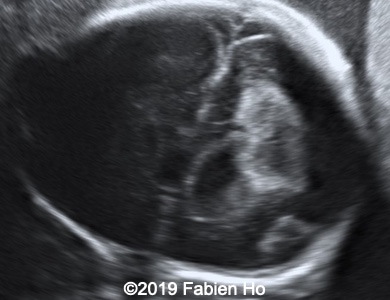

Images 1-3: in the left frontal lobe, hyperechoic with hypoechoic center lesion within the deep and periventricular white matter. Interestingly, this lesion has no mass effect on the lateral ventricle, and it has smooth margins.

Images 12-16: we performed a second fetal brain MRI at 32 weeks, which showed the same findings as the postnatal neonatal brain MRI as follows:

The evolution of the images is typical of a clastic lesion: after resorption of the ischemic tissue and hematoma, there was now a focal porencephaly with hemosiderin tattooing on its margins. Conversely, persistence of the same MRI findings would have indicated an hypercellular brain tumor, which could have been a differential diagnosis.